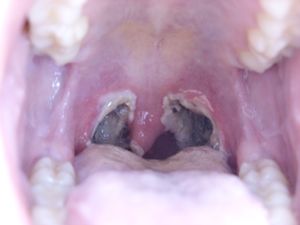

편도절제술은 편도염이나 수면 무호흡증 치료를 위해 시행되는 수술이다. 의학적 용도로는 편도 주위 농양, PFAPA 증후군, 코 기도 폐쇄, 편도암, 디프테리아 보균 상태 등이 있으며, 소아의 경우 아데노이드 제거술과 함께 시행되기도 한다. 잦은 인후통, 즉 편도염의 경우, 지난 1년 동안 7번 이상, 지난 2년 동안 매년 5번 이상, 또는 3년 동안 매년 3번 이상의 인후 감염이 있는 경우에 권장된다. 수술 방법으로는 메스, 전기 소작, 고주파 열 절제, 코블레이션, 하모닉 메스, 열 용접, 이산화탄소 레이저, 미세 절제기 등이 사용된다. 수술 후에는 인후통, 출혈, 탈수 등의 합병증이 발생할 수 있으며, 회복 기간 동안 적절한 수분 섭취가 중요하다.

편도절제술은 주로 수면 무호흡증과 재발성 또는 만성 편도염에 시행된다.[1] 편도 주위 농양, 주기적 발열, 아프타성 구내염, 인두염 및 림프절염 (PFAPA), 물방울 건선, 코 기도 폐쇄, 편도암, 디프테리아 보균 상태의 경우에도 시행된다.[1][2] 소아의 경우 아데노이드 제거술과 함께 시행되기도 하지만, 아데노이드 제거가 재발성 인후통 치료에 추가적인 영향을 미치는지는 불분명하다.[2]

편도 결석, 구취, 삼킴 곤란, 그리고 소아의 비정상적인 목소리와 같은 경우에도 편도절제술이 고려될 수 있지만, 이에 대한 확실한 증거는 없다.[1]3. 합병증

일반적으로 편도절제술은 안전하지만, 여러 가지 합병증을 유발할 수 있으며, 이 중 일부는 심각하다.[1][2] 합병증은 일차성(수술 후 24시간 이내)과 이차성(24시간 이후)으로 나뉘며, 출혈이 가장 흔한 합병증이다. 다른 흔한 합병증으로는 수술 후 오심 및 구토, 탈수, 음식 섭취 곤란, 귀 통증, 미각 이상 및 말하기 곤란 등이 있다.[1][20] 드물게 편도절제술은 치아 손상(수술 중 입안에 삽입되는 클램프 때문에), 후두 및 인두 벽 손상, 흡인성 폐렴, 호흡 곤란, 후두경련, 후두 부종 및 심정지를 유발할 수 있다.[1] 목의 통증은 수술 후 약 1~2주 동안 지속된다.[1][5]

4. 수술 방법

편도절제술은 다양한 방법으로 시행될 수 있다. 지난 50년간은 주변 근막에서 편도선을 절개하는 완전 절제술이 주로 시행되었으나, 최근에는 합병증을 줄이기 위해 부분 편도 절제술(편도 절개술)에 대한 관심이 높아지고 있다.[33]